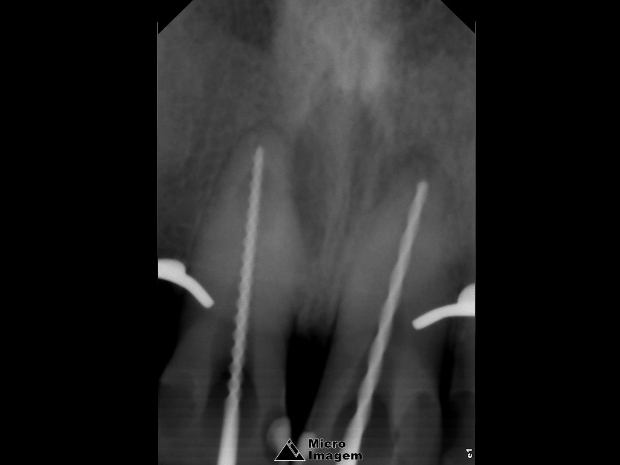

Após a abordagem inicial do paciente, o mesmo foi anestesiado e procedeu-se à confecção do isolamento absoluto. Posteriormente, o acesso coronário foi realizado, onde se constatou clinicamente a necrose pulpar de ambos os dentes. Foi realizada uma penetração desinfetante crown-down empregando como agente irrigador NaOCl a 5%, sendo a odontometria realizada pelo método radiográfico, devido a inviabilidade de emprego de um localizador foraminal nestas condições anatômicas, podendo influenciar em sua precisão (figura 4).

- Figura 4